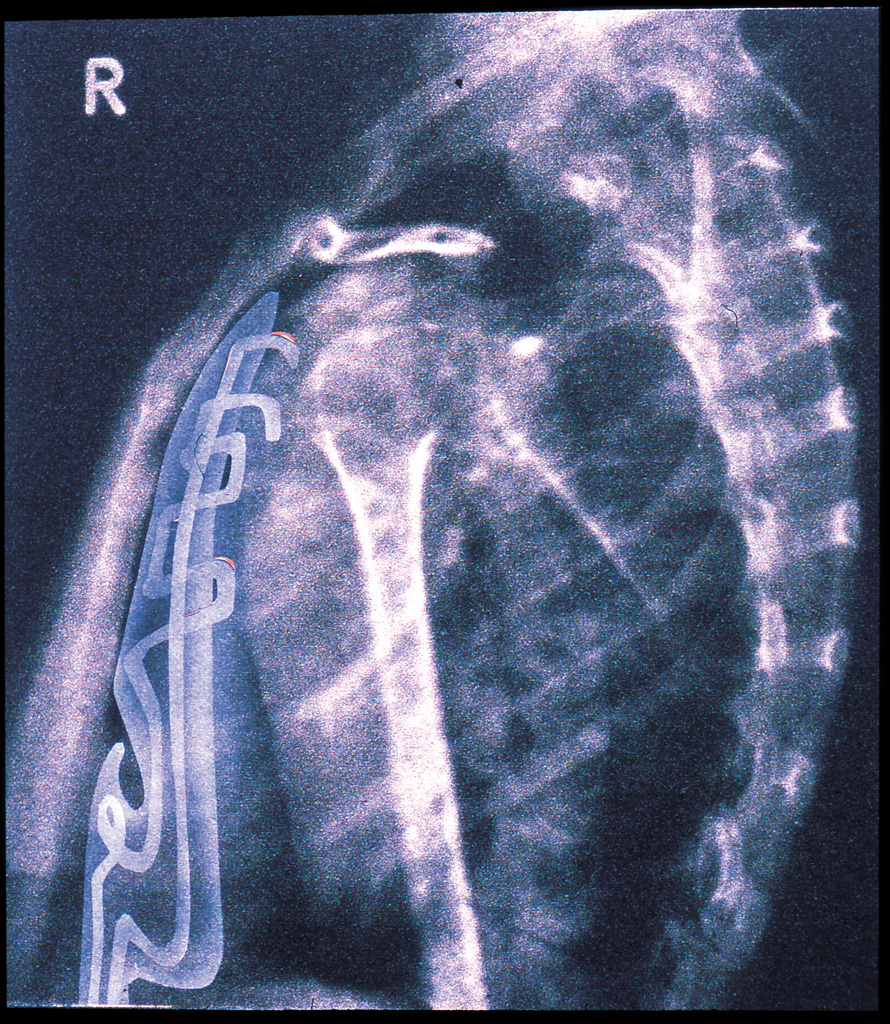

I have just returned to some drawings I made many years ago. I had a request to put them in an exhibition, which might interfere with a couple of other exhibitions that are coming up, so I have made some copies with slight alterations. It is part of the second body project (see here and here) where I altered X-ray photographs of the body and the related positioning photographs to take those X-rays. The positioning pictures (the originals are taken from Positioning in Radiography by K.C. Clark, 1949 edition) have slight bumps on the body that reveal the synthetic organs through formal transparency. I have not altered these much but have developed the X-ray images by spraying transparent cool grey on the interior of the synthetic organs and added soft highlights, which gives a transparency closer to that in an X-ray.

The stereoscopic anatomical drawings describe the apparatus to make an internal architecture. THis sequence of paired drawings discusses the revelation of the architecture in both a practical way but also by implication a sense of the larger spatial consequence of the project. Each pair of drawings has an X-ray and a photographic illustration of the position the body has to hold to take that X-ray. The base images (except for the final X-ray) are taken from Positioning in Radiography by K.C. Clark (1949 edition). Francis Bacon worked from images in the 1939 edition of the same book.

Each X-Ray shows parts of the new body apparatus but they are available to this sort of inspection selectively, so not everything is visible. The positioning photographs display a formal transparency of the apparatus, again selectively as only those parts that press against the skin are visible.

In the positioning picture (2B) you can see a filter under her skin just above her forearm and the top of the breathing/cooling components just below her collar bone, the piece that is visible in the X-ray.

X-Ray 3A is not from Positioning in Radiography, but 3B is, the positioning to take the image in 3A. The X-Ray shows the selective revelation of the intestines through the agency of a barium meal – tissue that would otherwise be transparent to X-Ray shows up due to the meal. The image is unlikely, as the synthetic organs of the new apparatus should divert toxins through the synthetic system (and therefore reveal them more fully) so we have to assume that the apparatus has been turned off to check the natural organs. In the positioning photograph you can again see discrete bumps around her waist and abdomen where the apparatus pushes into the skin.